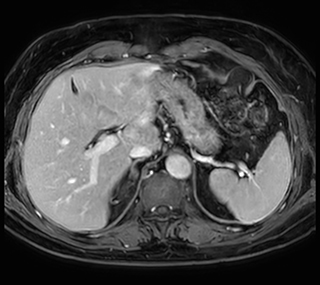

Performed on Ingenia Ambition. FOV 430 mm, voxels 1.3 x 1.3 x3.0 mm, 130 slices, Breath hold 16.6 sec

Using mDIXON provides excellent fat saturation uniformity. No artifacts seen at the edges in these images, while these were quite commonly seen with eTHRIVE on our previous system. Note also the high resolution.

Ingenia Ambition, 3D breath hold, FOV 370 mm, voxels 1.51 x 1.58 x 4.0 mm, 120 slices, scan time 19.6 sec.